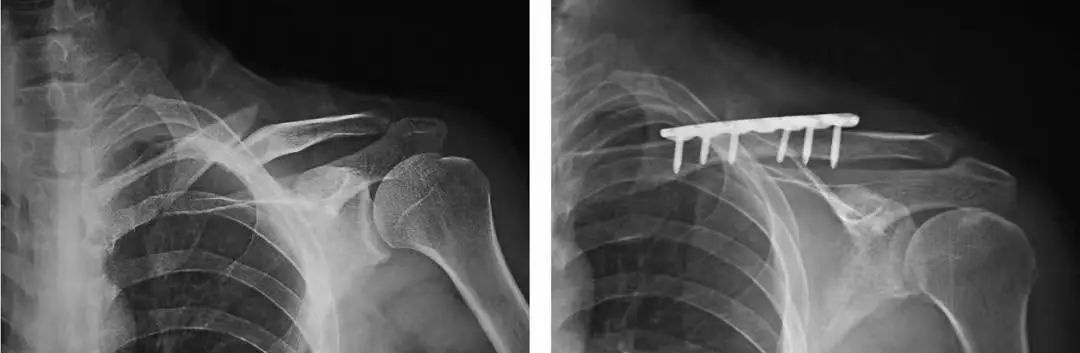

手术治疗:主要手术方式有髓内固定接骨板系统两种。

手术治疗的绝对适应证包括:开放骨折、合并血管损伤、进行性神经受损的表现、漂浮肩、移位的病理骨折以及原始骨折短缩>2cm。相对适应证包括:合并有多发伤、皮肤受损潜行剥脱、双侧锁骨骨折、无法忍受长时间制动、对外形美观有较高要求以及存在帕金森症、癫痫、颅脑损伤等神经精神情况。

锁骨板有哪些【每周科普】锁骨骨折分中段、外段、内段,治疗方式也有差异_https://www.jmylbn.com_新闻资讯_第12张

锁骨中段骨折的接骨板内固定手术